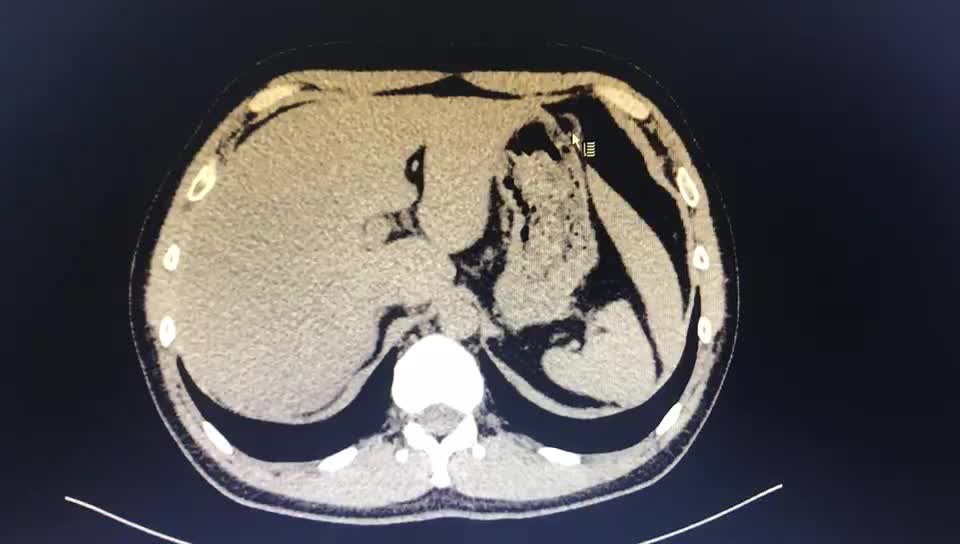

上图,重建图像下黄色箭头指向降结肠成串的结肠憩室,没有发炎.